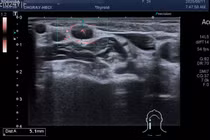

Bệnh nhân H.V.V, 25 tuổi, nhập viện tại Trung tâm Y tế khu vực Đoan Hùng trong tình trạng xuất hiện khối sưng đau vùng cạnh hậu môn trái kéo dài khoảng 1 tuần. Qua thăm khám lâm sàng kết hợp chụp cộng hưởng từ vùng chậu, bác sĩ phát hiện hình ảnh đường rò hậu môn - một bệnh lý thường hình thành sau viêm hoặc áp xe quanh hậu môn.

Nhận định đúng tình trạng bệnh, ê-kíp phẫu thuật của Trung tâm đã tiến hành phẫu thuật cắt đường rò hậu môn cho người bệnh. Ca mổ diễn ra thuận lợi, an toàn, toàn bộ đường rò được xử lý triệt để.

Sau phẫu thuật, bệnh nhân được chăm sóc, rửa vết thương hàng ngày, sử dụng thuốc kháng sinh và giảm đau nhằm giảm sưng nề, ngăn ngừa nhiễm trùng và giúp vết mổ mau liền. Hiện tại, vết mổ khô, bệnh nhân ổn định, đang được tiếp tục theo dõi tại khoa.